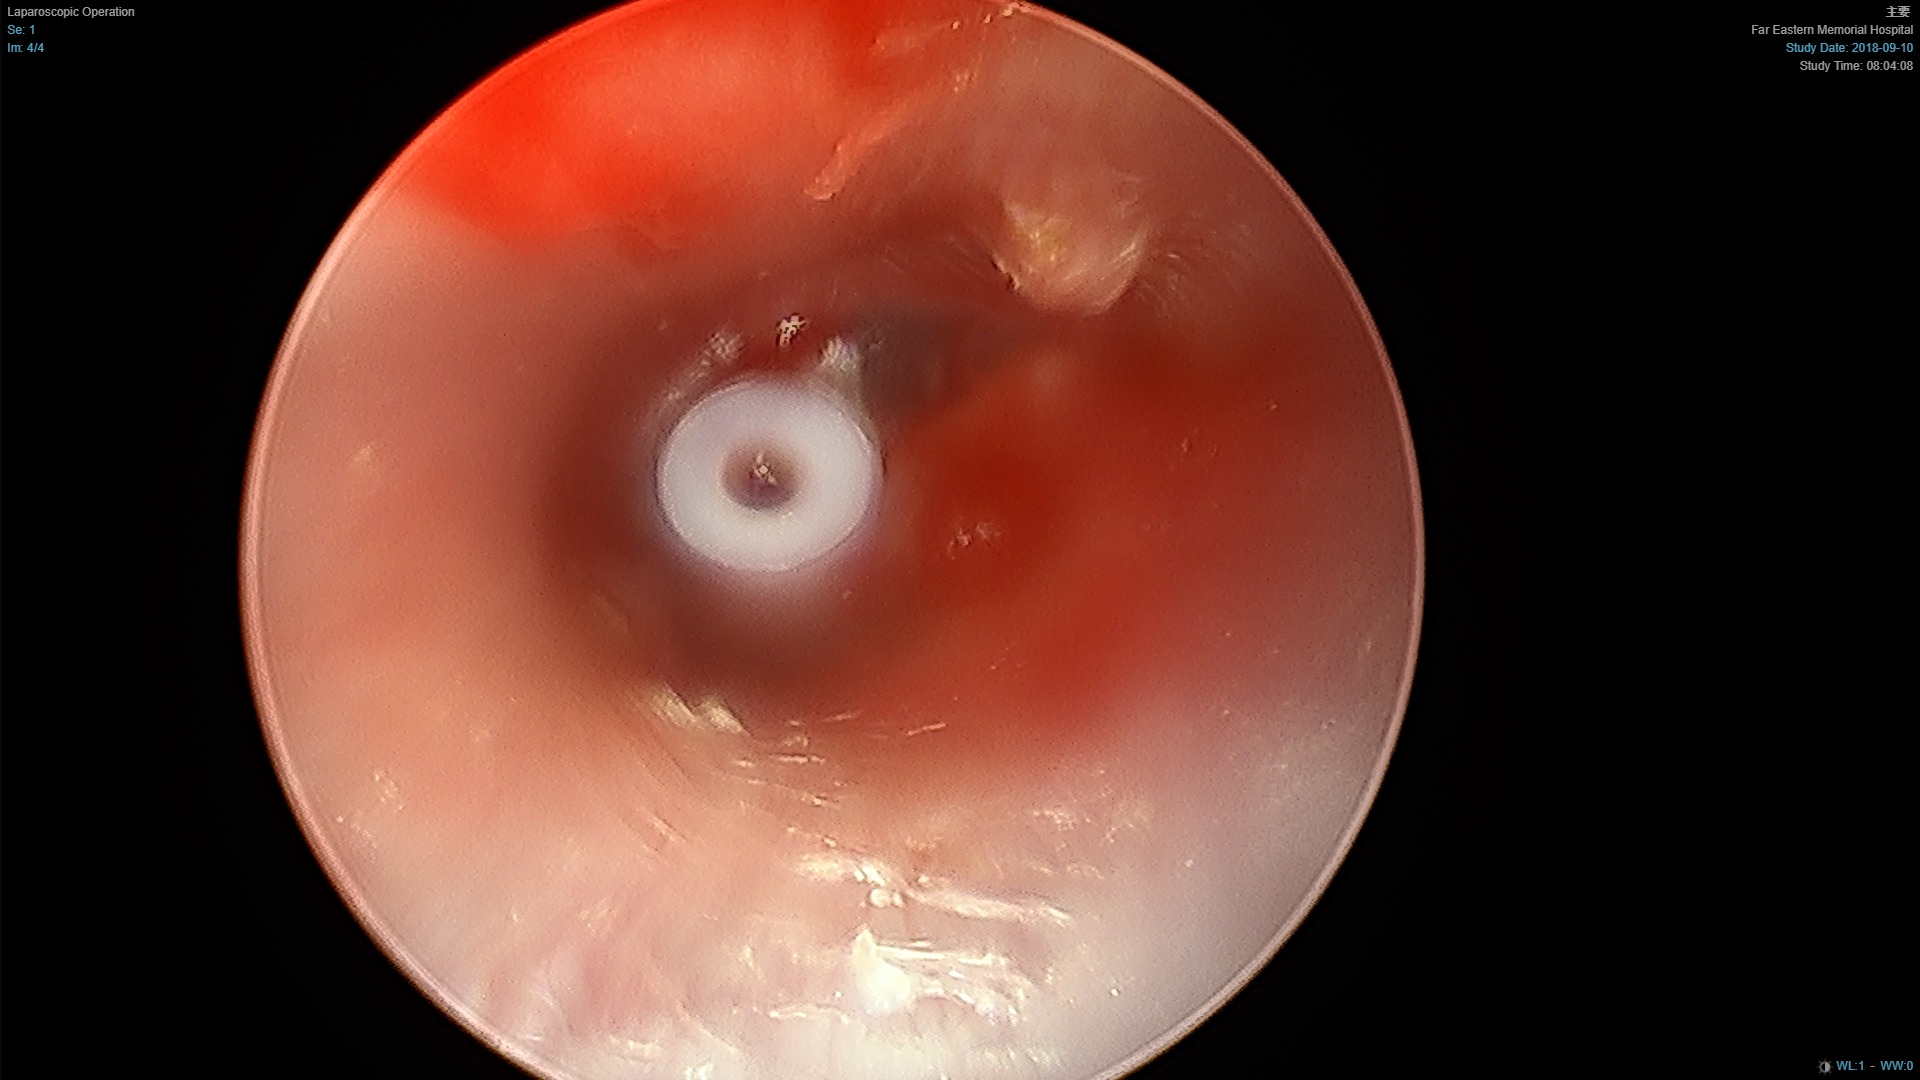

中耳積液

中耳通氣管(約2.7mm)

中耳積液超過三個月,或聽力影響較大,會建議置放中耳通氣管。